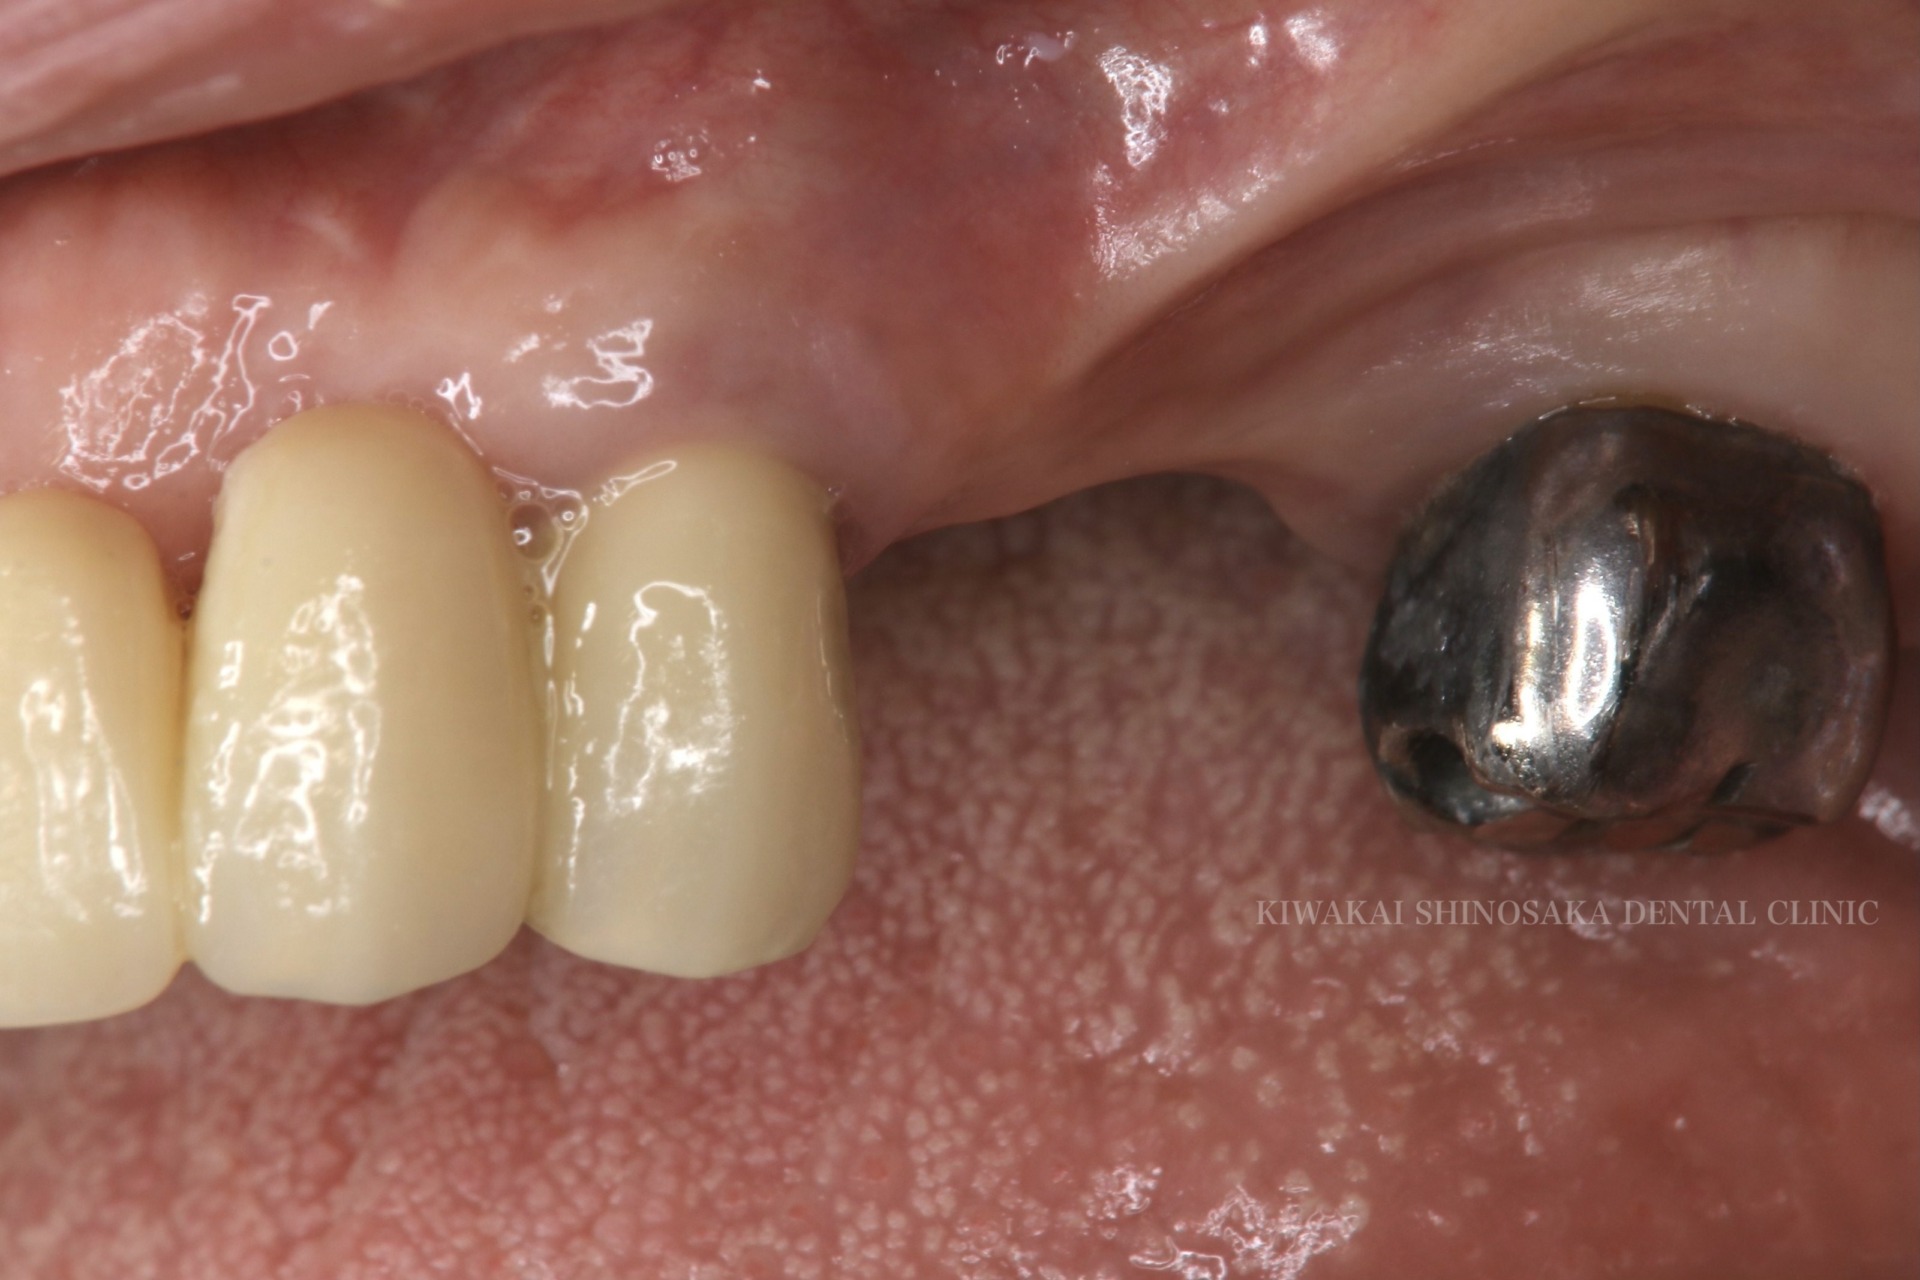

手術部位が生着したのを確認後、インプラント体の上部にロケーターアタッチメントを取り付け、新しく作製した義歯を装着しました。

義歯装着後は、主訴にあった疼痛や違和感はなくなり、快適にお過ごしいただいています。